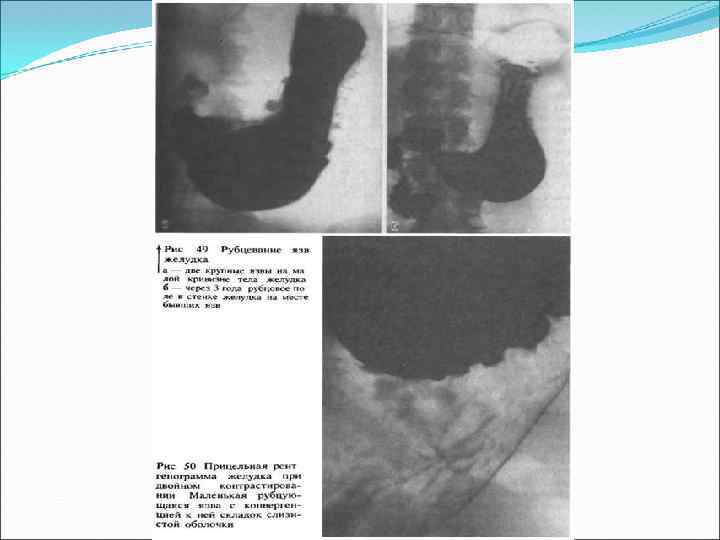

Рентгенологическое обследование в настоящее время носит вспомогательный характер. Используется преимущественно для диагностики моторно-эвакуаторных нарушений, дуоденостаза, рубцово-язвенных деформаций желудка и ДПК. С диагностической целью при абсолютных противопоказаниях к эндоскопии. Рентгенологические критерии язвы: симптом "ниши", конвергенция складок и т. д. встречаются редко

Доброкачественное язвенное поражение антрального отдела желудка.